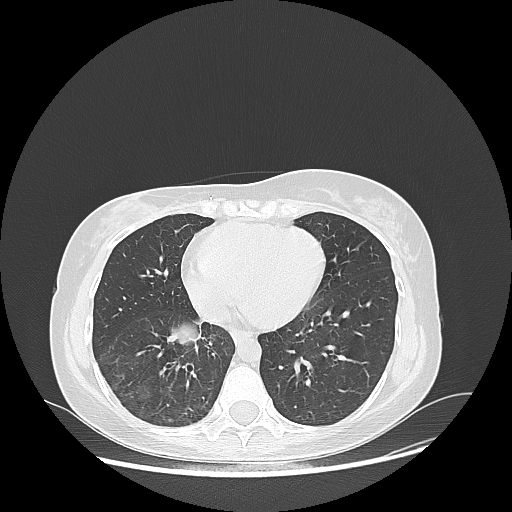

Image Grid

4Γ—3 grid: Rows show different image types (Original NATIVE, Reconstructed NATIVE, Original VENOUS, Generated VENOUS), Columns show windowing techniques (No Window, Lung Window, Mediastinum Window)

Generated VENOUS CT scan (A→B translation)

Full window (WL 1023.5, WW 4095 β†’ Low βˆ’1024, High +3071)

Lung window (WL -600, WW 1500 β†’ Low βˆ’1350, High +150)

Mediastinum window (WL 40, WW 400 β†’ Low βˆ’160, High +240)